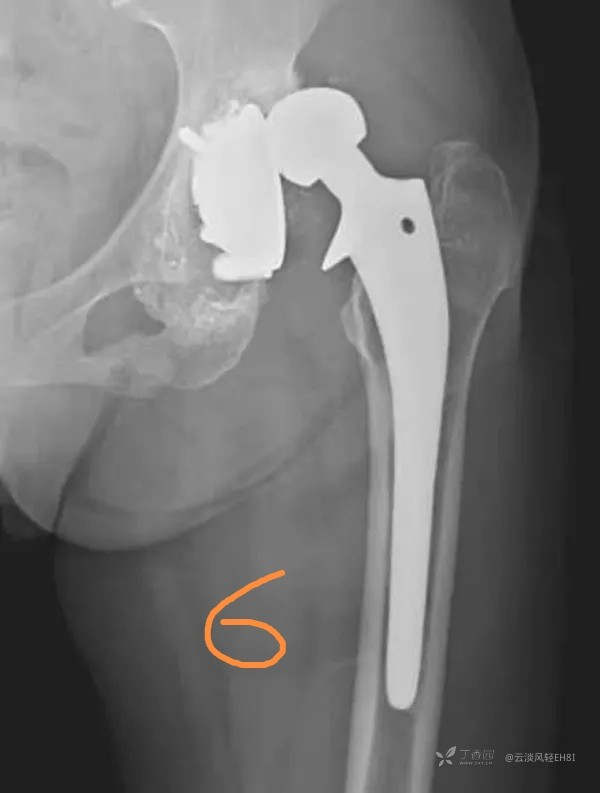

六、假体移位(图6)

假体移位时,在X线片上可显示髋臼假体方向有改变,轻度移位表现为骨水泥与骨界面或骨水泥与髋臼假体界面之间的间隙增宽。显著移位则髋臼假体松脱并明显向上移位;股骨假体移位可发生在骨水泥与骨界面或金属假体与骨水泥界面之间,也可沉入股骨髓腔中或移向内翻位(即股骨假体末端贴近股骨外侧皮质,正常情况下,应呈轻度外翻位即股骨假体末端贴近内侧皮质)。